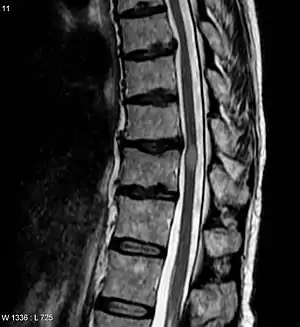

An area postrema lesion in association with leptomeningeal enhancement and intraparenchymal BBB breakdownSpinal cord MRI (A–C) and brain MRI (D–G) from an AQP4-IgG–positive patient with NMOSD who presented with recurrent myelopathy of 1 month duration and area postrema lesion, which progressed into LETM. Images were obtained during acute attacks. An area postrema lesion (A) in association with subacute progression to LETM with leptomeningeal and intraparenchymal T1W contrast enhancement (arrows, B). The spinal cord lesions were also demonstrated on T2W and STIR images (C). Cerebral MRI during another attack with periependymal enhancement on T1W images at the lateral (D) and third ventricles (F). FLAIR images showing lesions along lateral ventricle (E), thalamus, and hypothalamus (G). (B) Used with permission of the publisher from Flanagan EP, Weinshenker BG. Neuromyelitis optica spectrum disorders. Curr Neurol Neurosci Rep 2014;14:483. Copyright © 2014, Springer Science+Business Media New York. AQP4-IgG = aquaporin-4 immunoglobulin G; BBB = blood-brain barrier; FLAIR = fluid-attenuated inversion recovery; LETM = longitudinally extensive transverse myelitis; NMOSD = neuromyelitis optica spectrum disorder; T1W = T1 weighted; T2W = T2 weighted. | |